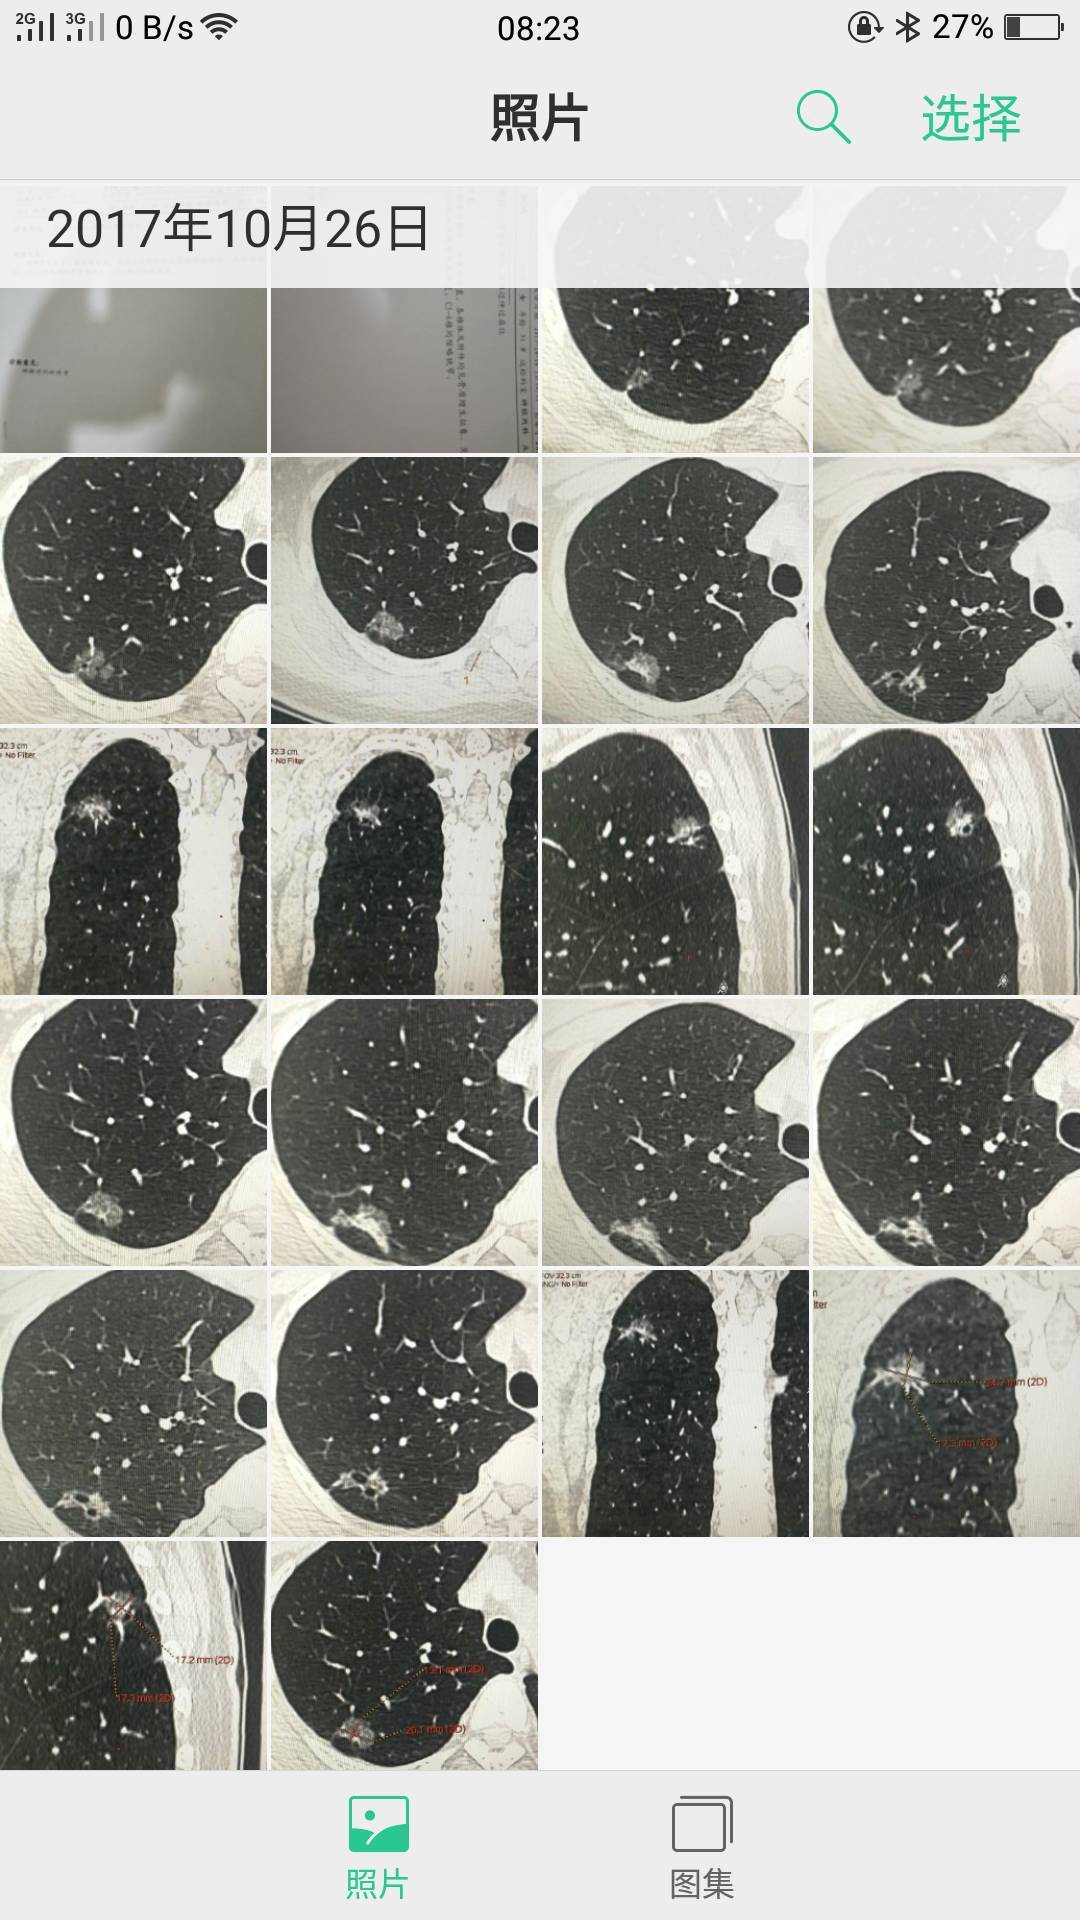

您好,陈大夫,我的图片都是别人从电脑里发给我的,我一点也看不懂哪个是左肺的哪个是右肺的,这就是所有的图了,我这样发给你不知道行不行?谢谢您了,认真负责的好大夫啊!现在这样的大夫少见啊!

这张

这张

陈波医生把左右两边的一起拍一个镜头里,应该还是局限在右上肺的原位癌,但还是想看全肺把其他地方排除一下

陈波医生有时间把CT报告发我看看,你是哪个省的,你这个要找手术做得好的,肺癌治疗这个概念太广了